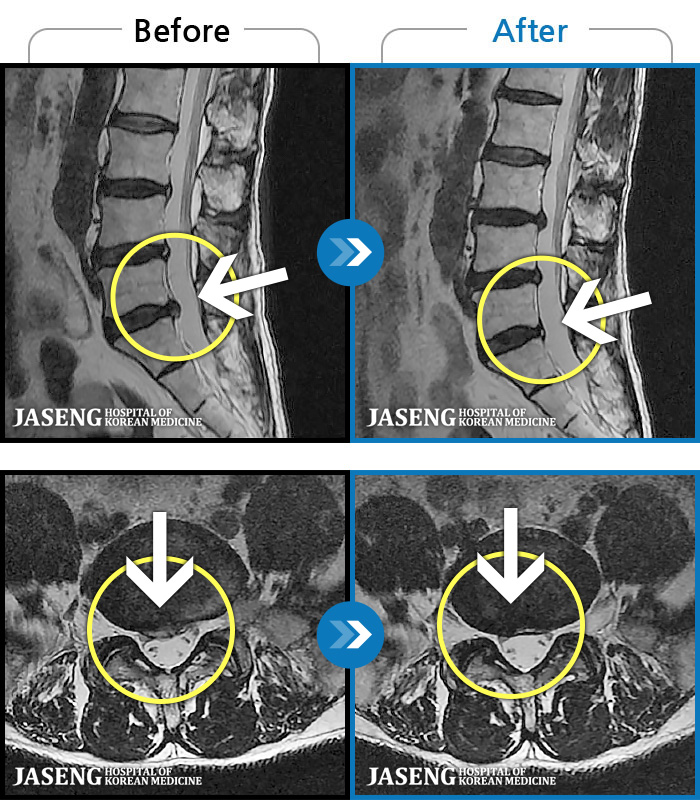

허리통증이 심해서 숙이기 어렵고 차에서 내리기 힘들었습니다.

2021.01.06 ~ 2025.03.10